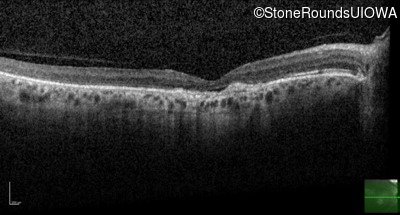

Optical Coherence Tomography - Right - 20/100

Exemplar / OCT Stack

Optical Coherence Tomography - Left - 20/100